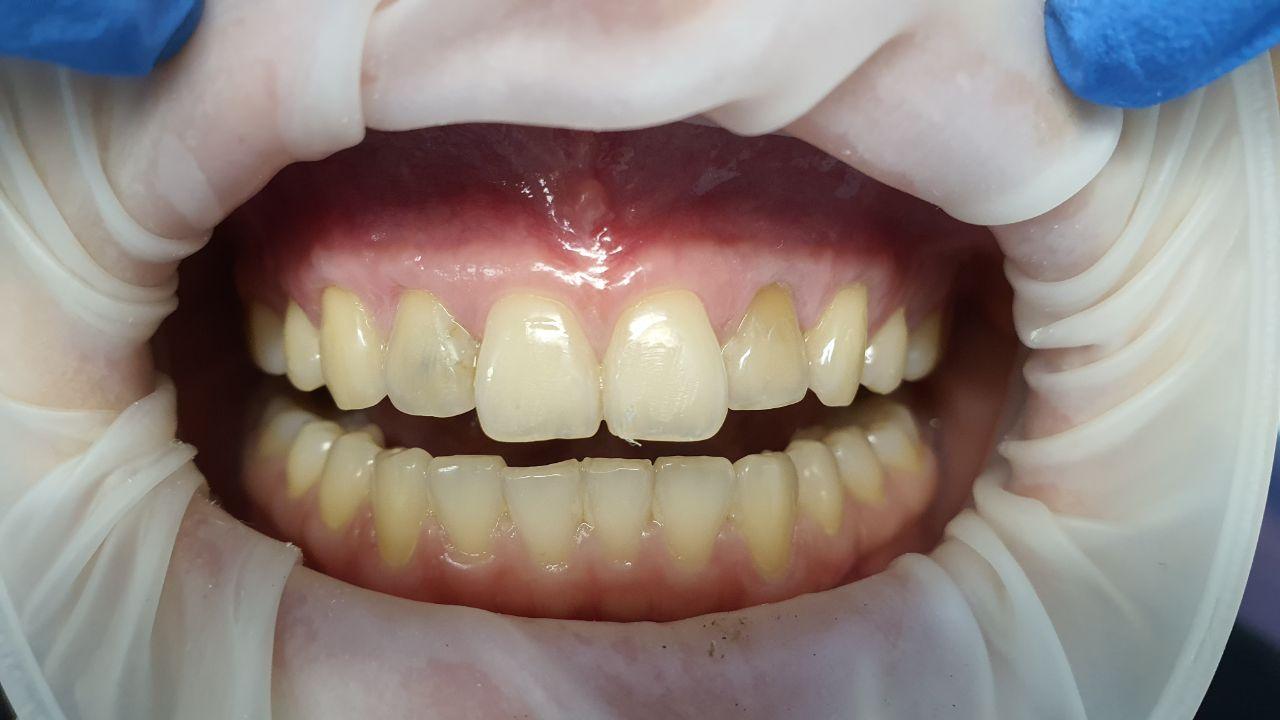

Гингивит- воспаление десны, обусловленное неблагоприятным воздействием местных и общих факторов и протекающее без нарушения целостности зубодесневого нарушения. Гингивит чаще наблюдается у детей и лиц молодого возраста, также у беременных.

Пародонтит- воспаление десен с нарушением целостности зубодесневого соединения, сопровождающееся образованием патологического кармана и убылью костной ткани. Поражает практически все возрастные группы населения, в том числе молодых людей и даже детей. Именно они приводят чаще всего к потере зубов вследствие выраженного деструктивного процесса, обусловливая стойкие нарушения функции зубочелюстной системы.

- Кровоточивость

- Гиперемия и отек десны

- Чувство зуда

- Подвижность зубов

- Обнажение корней зубов